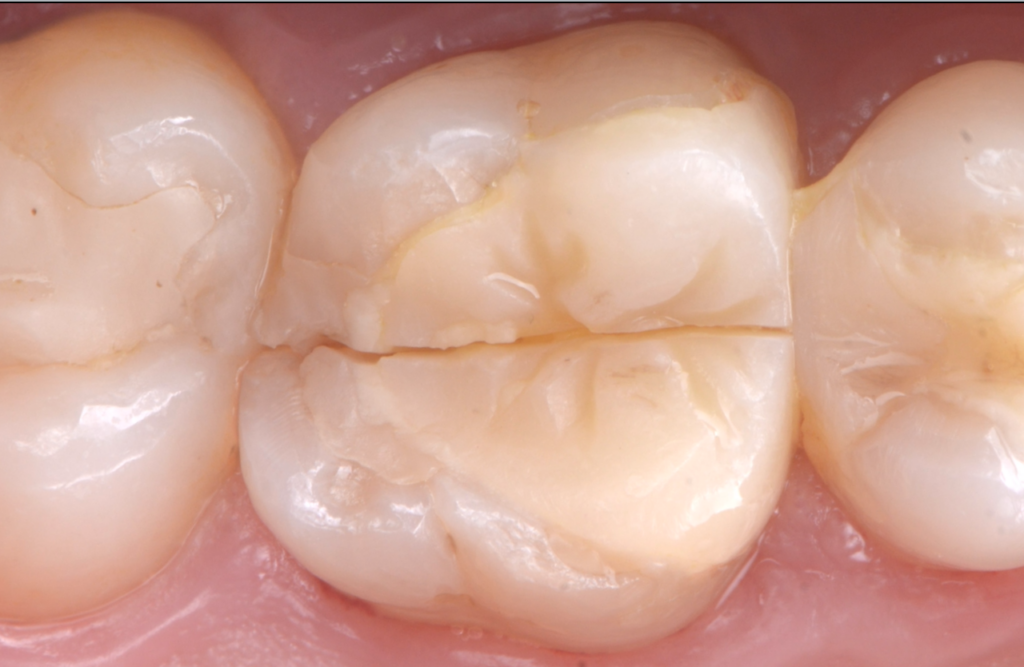

Nouvel onlay de la part de notre correspondante